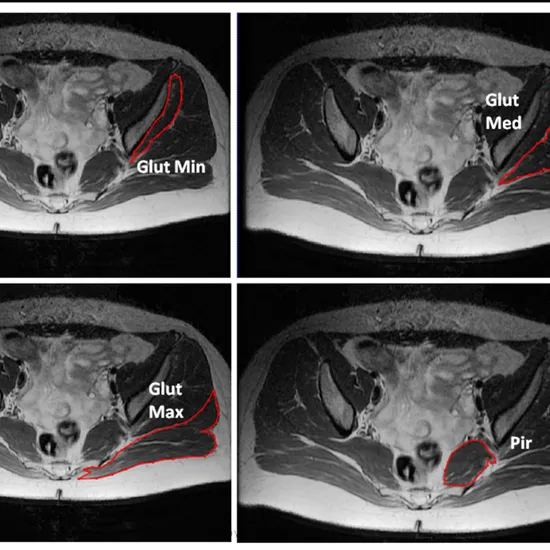

Buttocks MRI is a non-invasive radiology test that can be done without pain to look at the area of the buttocks. It helps doctors figure out what's wrong with the muscles in the buttocks area.

Doctors usually order a buttock MRI to help diagnose Piriformis syndrome. Buttock pain, tingling, or numbness are the most common first symptoms. Serious pain that travels down the length of the sciatic nerve is referred to be "sciatica'" (called sciatica).

MRI (Magnetic Resonance Imaging) spine is a non-invasive medical diagnostic tool used to obtain detailed images of the buttocks and surrounding tissue. MRI of the gluteal region is used to show abnormalities like Piriformis syndrome. Buttock pain, tingling, numbness etc.